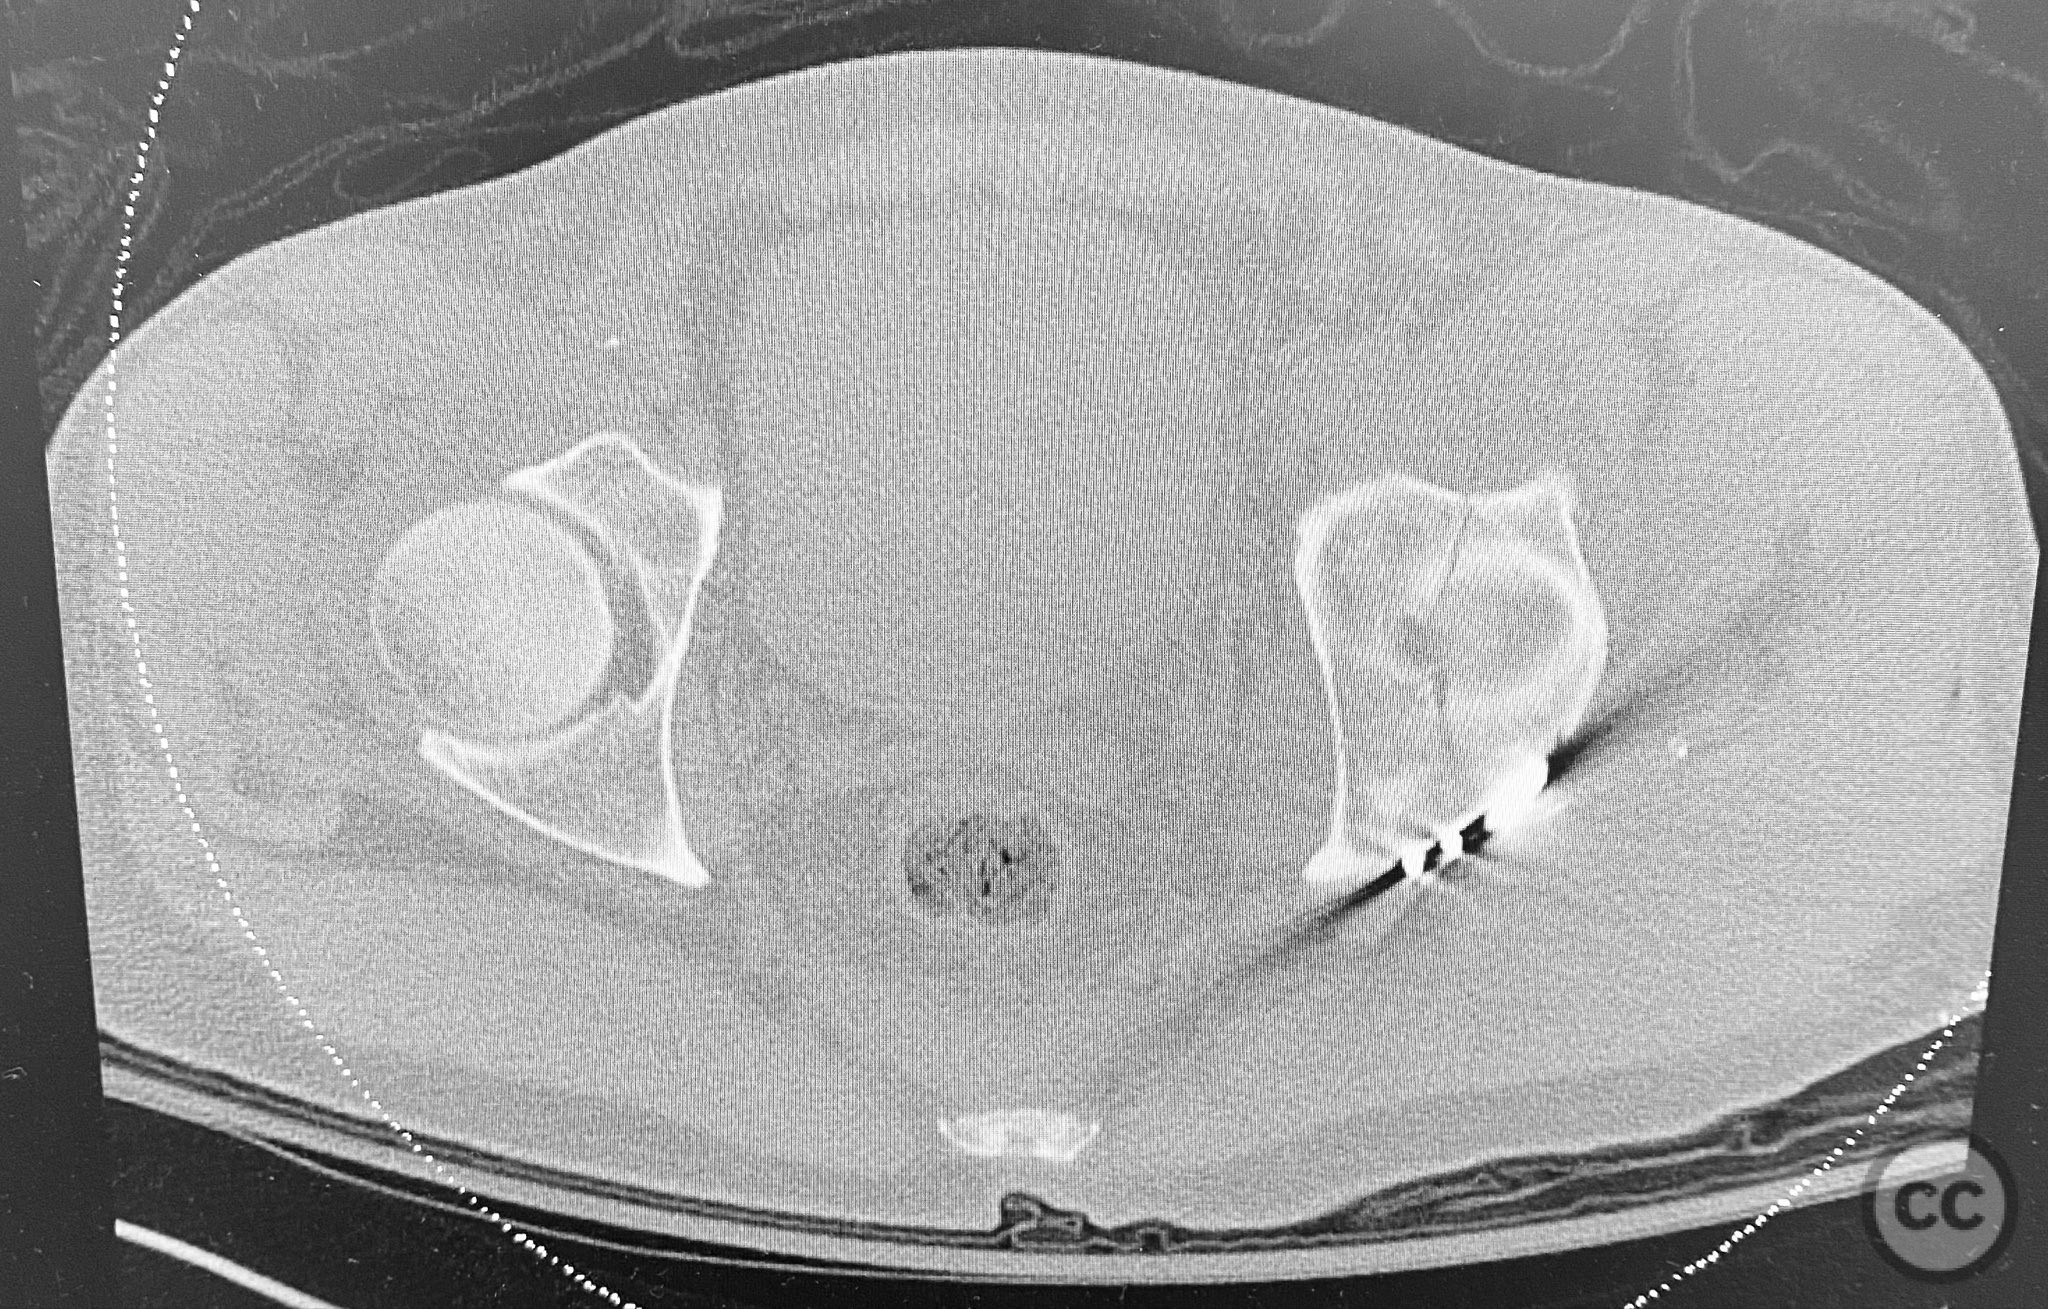

Clinical and radiological findings:  A patient presented with a seemingly non-comminuted, wide, and long posterior wall (PW) acetabular fracture fragment. Axial computed tomography (CT) images demonstrated the thickness of the PW fragment, the articular surface, and multiple areas of subchondral impaction. Preoperative planning identified the size, location, and depth of the impaction zones, as well as an essentially nondisplaced transverse acetabular fracture line, which was not readily apparent on initial imaging. No significant displacement of the transverse component was noted. The AO/OTA classification is 62-B1.3 (posterior wall and transverse acetabular fracture).